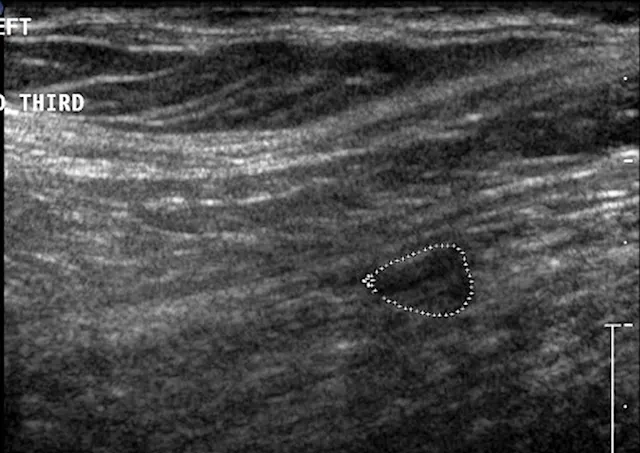

The iliopsoas muscle consists of the iliacus and psoas major muscle groups, which originate along the lumbar spine and ilium and insert on the lesser trochanter of the femur. Its main function is to flex and externally rotate the hip. Injury can occur secondary to an acute excessive force or repetitive use and/or trauma, resulting in a mild-to-severe pelvic limb lameness.7-10 Pain often can be elicited on examination by extension and internal rotation of the hip joint, abduction of the femur, and direct palpation of the muscle–tendon junction near the lesser trochanter.7-10 Because the femoral nerve runs through the iliopsoas muscle, some dogs that strain this muscle may also develop a peripheral neuropathy from compression of the nerve.8,9 Standard radiography can identify mineralization in the tendon, whereas ultrasonography, CT, and MRI are helpful for identifying early and subtle lesions and can help direct therapy (Figures 5 and 6).8-10 Mild-to-moderate acute lesions can often be treated with medical management (eg, rest, NSAIDs, physiotherapy, platelet-rich plasma injections).10 If the lesion is severe and results in fibrosis or contracture of the muscle, a partial tenectomy may be indicated.8,10

Ventrodorsal radiographic projection of a 9-year-old dog with right hindlimb lameness and hip pain. In addition to bilateral hip dysplasia and secondary osteoarthritis, mineralization is present within the right iliopsoas muscle near the tendon insertion on the lesser trochanter (arrowhead), which indicates a chronic strain injury.